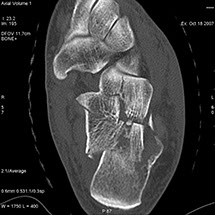

Cet appareil permet de faire des images en coupe du corps humain

et de les reconstruire dans différents plans pour mieux visualiser

Le scanner comporte un lit d'examen, sur lequel le patient est allongé, qui va se déplacer lentement pendant l’examen et un anneau qui va tourner autour du patient en émettant des rayons X (il contient le tube à rayons X et les récepteurs). Les rayons X vont traverser la région à étudier et permettre d’obtenir des images en coupe de la zone à étudier. Des traitements de numérisation informatique permettront d'obtenir  des images 2D ou 3D dans différents plans et volumes.

Grâce aux scanners multidétecteurs (ou multi-barrettes) à acquisition spiralée, on obtient une exploration très précise d'un large volume du corps humain pour un temps d'acquisition de quelques dizaines de secondes.

• Les examens et mesures orthopédiques (malformations, fractures et évolution, étude de la structure osseuse).